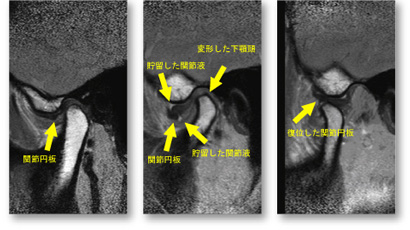

【裁断済み】顎関節の画像診断 : 臨床医によるMRI・CT読像の手引き 顎関節の画像診断 臨床医によるMRI・CT読像の手引き/医歯薬出版株式会社

【裁断済み】「顎関節の画像診断 : 臨床医によるMRI・CT読像の手引き」大谷 昌 / 鷹木 雪乃 / 箕輪 和行 / 箕輪 和行 / 月岡 庸之 / 金田 隆 / 金田 隆 / 阿部 伸定価: ¥ 10000#大谷昌 #大谷_昌 #鷹木雪乃 #鷹木_雪乃 #箕輪和行 #箕輪_和行 #箕輪和行 #箕輪_和行 #月岡庸之 #月岡_庸之 #金田隆 #金田_隆 #金田隆 #金田_隆 #阿部伸 #阿部_伸 #本 #自然/医療・薬学・健康本文に書き込みなし。値下げできません。素人検品、素人保管です。ローラー痕や、上下面、ページ端に汚れなどがある場合があり、ご容赦願います。あくまで中古品のため、神経質な方はご遠慮ください。